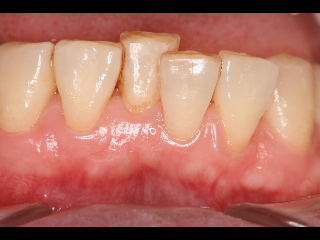

初診時、下の前歯の向かって左から2番目と3番目の間腫れています。

歯周病治療終了です、腫れはなくなりました。